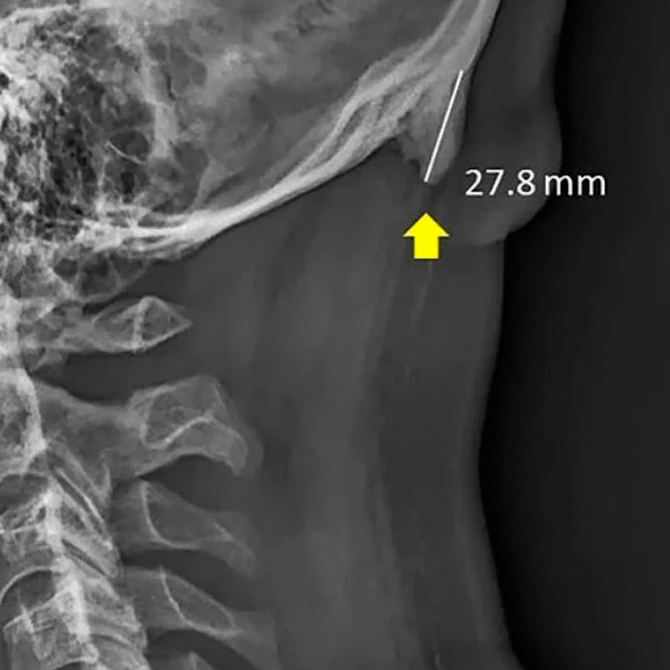

Научный журнал Scientific Reports исправил статью Дэвида Шахара, где говорилось о появлении рогообразного отростка на затылке у подростков. В первоначальной версии публикации говорилось, что рог вырастает из-за необходимости наклонять голову вперед, чтобы всматриваться в экран смартфона.